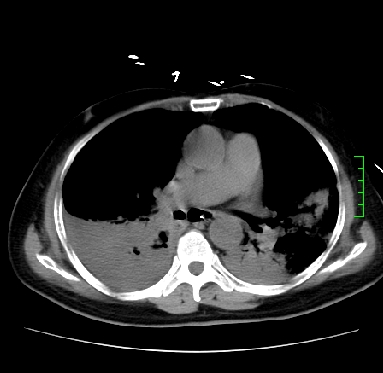

icu病人,几天都没明确诊断。m,76y,咳嗽、咳痰1周,伴气促,右胸痛入院,pe:t38.3c p135 r25 bp135/85。双肺可闻及大量湿罗音,心、腹未见明显异常。诊断:1心衰?2肺部感染?3冠心病?

11号ct

1)两肺感染性病变(右肺下叶肺脓肿可能)。2)双侧胸腔积液,以右侧为甚。

ards,肺感染性病变,右下叶实变,双侧胸腔积液,右侧为著,叶间胸膜积液,右上肺陈旧性tb纤维灶,左室大。

考虑:双肺感染、右肺下叶肺脓肿,双侧胸腔积液,肺水肿.请结合临床.